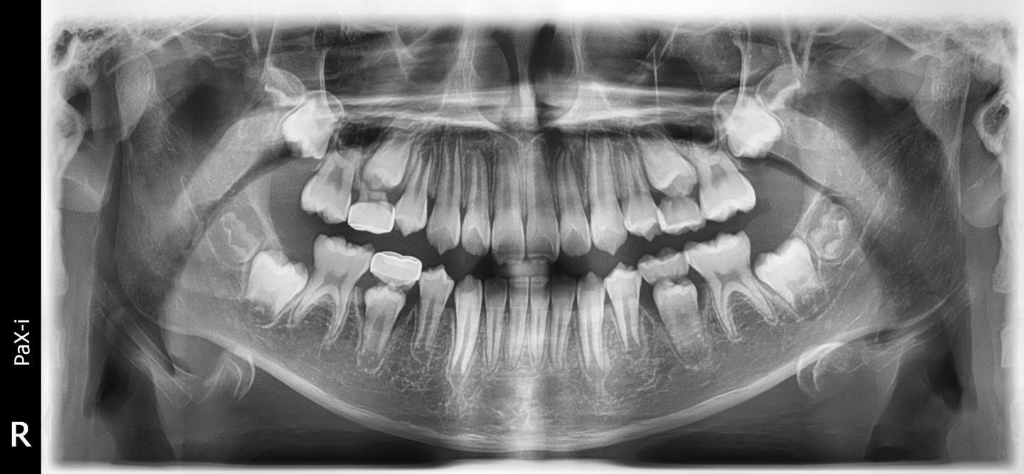

파노라마도첨부해요(파노라마사진은 아직 발치전 사진입니다. 현재는 이미발치해서 나오는중입니다)

방사선 사진과 추가된 임상 사진을 보니 치외치는 아닌 것 같습니다

물론 치외치 여부와 상관없이 소구치의 회전맹출로 교두가 위,아래 맞물릴 때 정확히 교합 지점을 찾지 못하여 깨지거나 마모되기 쉬운 것은 맞습니다

이미 어느정도 맹출하고 자리를 잡은 상태라 더 이상 여기서 올바르게 배열되기는 힘들 것 같습니다